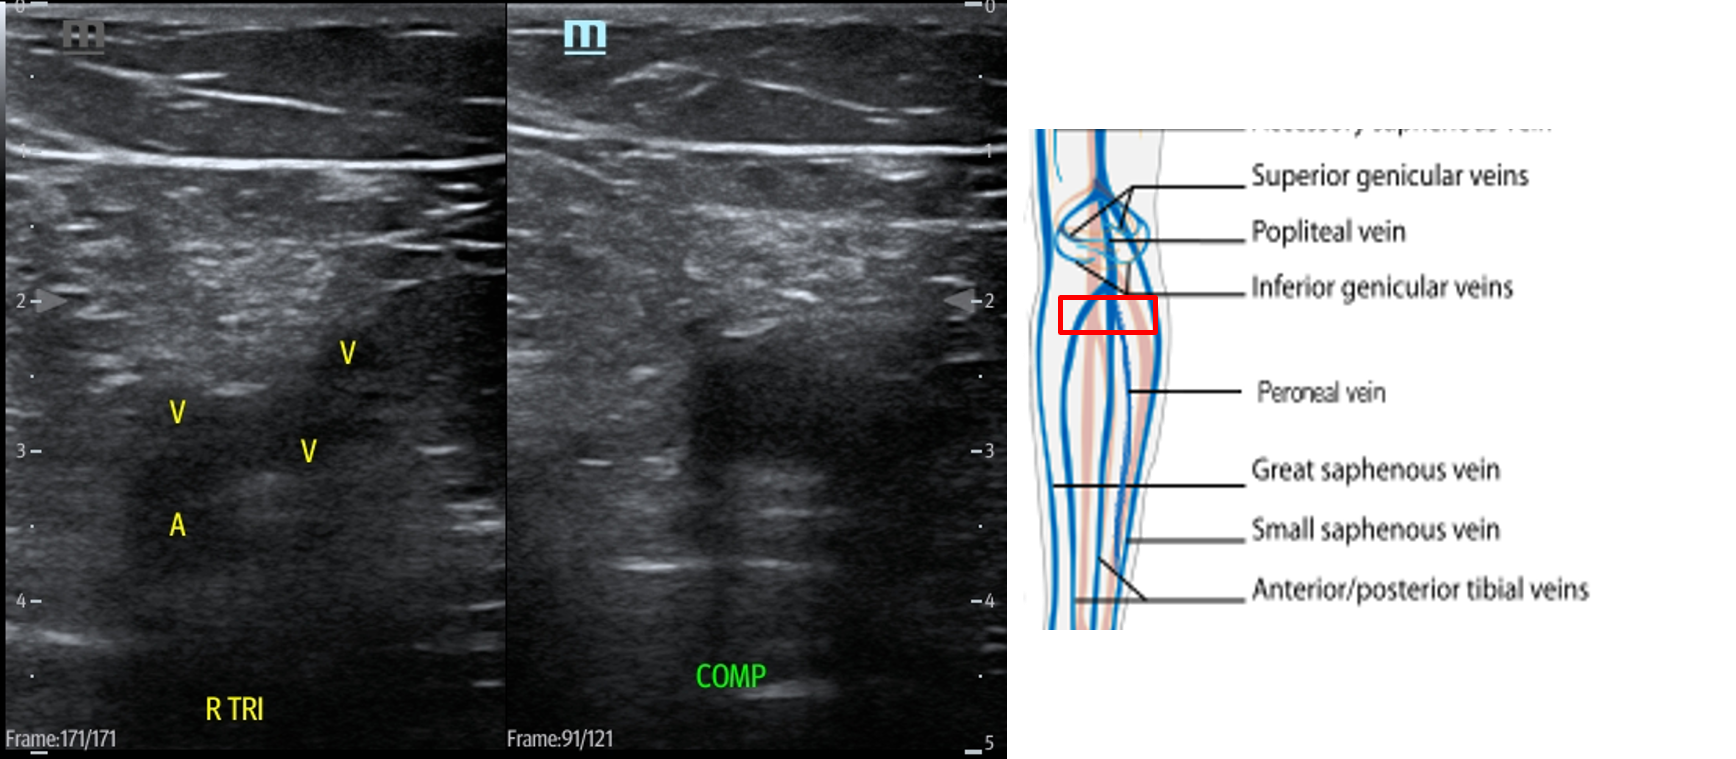

- Slide the transducer distally until you see the PV trifurcate into the PTV, ATV and peroneal vein. (Fig. 15) Compress each of these veins. This constitutes completion of evaluation of “region 2.”

- Figure 15. Compression of the PTV, ATV and peroneal vein in the distal portion of the popliteal fossa just before they converge into the popliteal vein with transducer orientation indicated (red rectangle).

- The PV will quickly trifurcate in the popliteal fossa. The visible tributaries in this region are the posterior tibial vein (PTV), anterior tibial vein (ATV), and peroneal or fibular vein ( 2, lower circle).